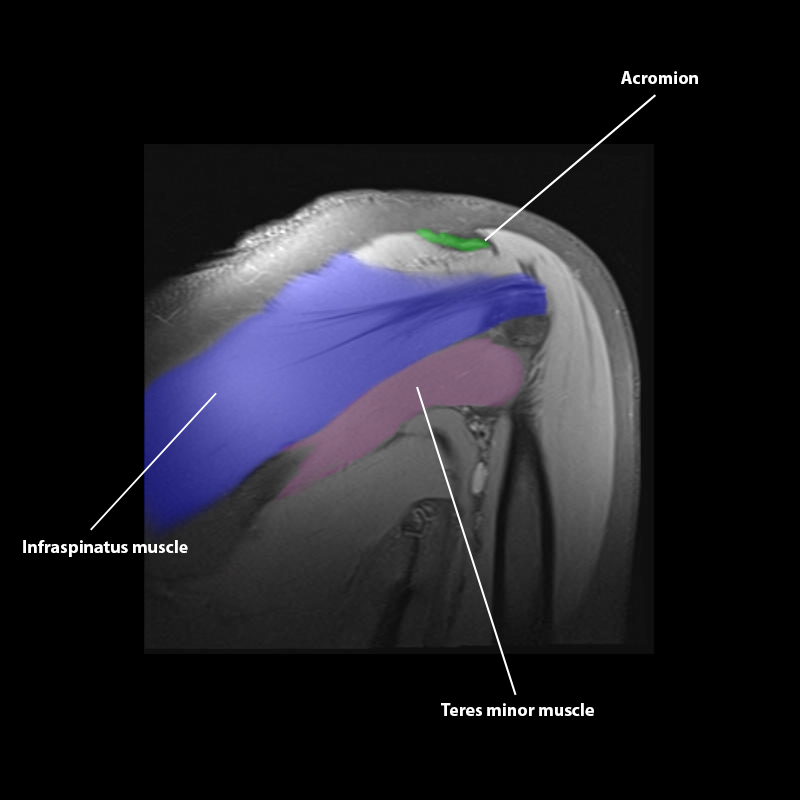

Shoulder MRI Anatomy